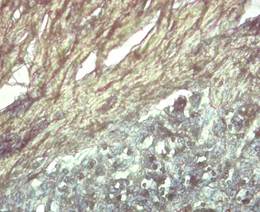

Figura 4. Coilocitosis en células epiteliales de la verruga y presencia de colágeno tipo I con birrefringencia verde amarillo en la dermis. Policromía y falta de homogeneidad del tejido. Coloración EVG 40X.

Elaboración: Los autores.

De igual forma, se observó vacuolización nuclear en el estrato espinoso de la epidermis (coilocitosis). En la coloración de Tricrómico de Van Gieson, donde se utiliza hematoxilina alcohólica, 10 % de cloruro férrico además de lugol, se 30 observó marcada proliferación dérmica de colágeno desorganizados con escasa presencia de tejido conjuntivo difuso (Figura 4).

Tal como plantearon Borzacchiello et al. (2008), histológicamente las lesiones causadas por papilomas son acantosis extensivas, desiguales y excrecencia epitelial. Las inclusiones intracitoplasmáticas, grandes, esféricas con manchas ácidas, a menudo rodeado por un halo